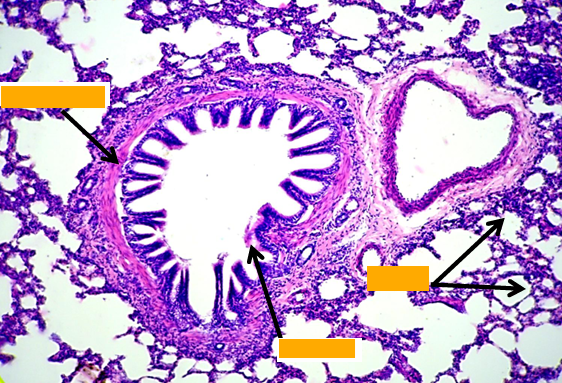

Intra pulmonary bronchus

1- epithelium, 2- smooth muscle, 3- cartilage

Bronchiole

Mucosa:

Epithelium: simple columnar to cuboidal partially ciliated with club cells

- Lamina propria: thin & contain elastic fibers.

Muscle layer: thin layer of circularly arranged smooth muscle.

- No goblet cells,

- No cartilage,

- No glands,

- No lymph follicles

Intrapulmonary bronchus

1. Epithelium

2. Smooth muscles spirally arranged

3. Plates of hyaline cartilage in adventitia

Terminal bronchiole